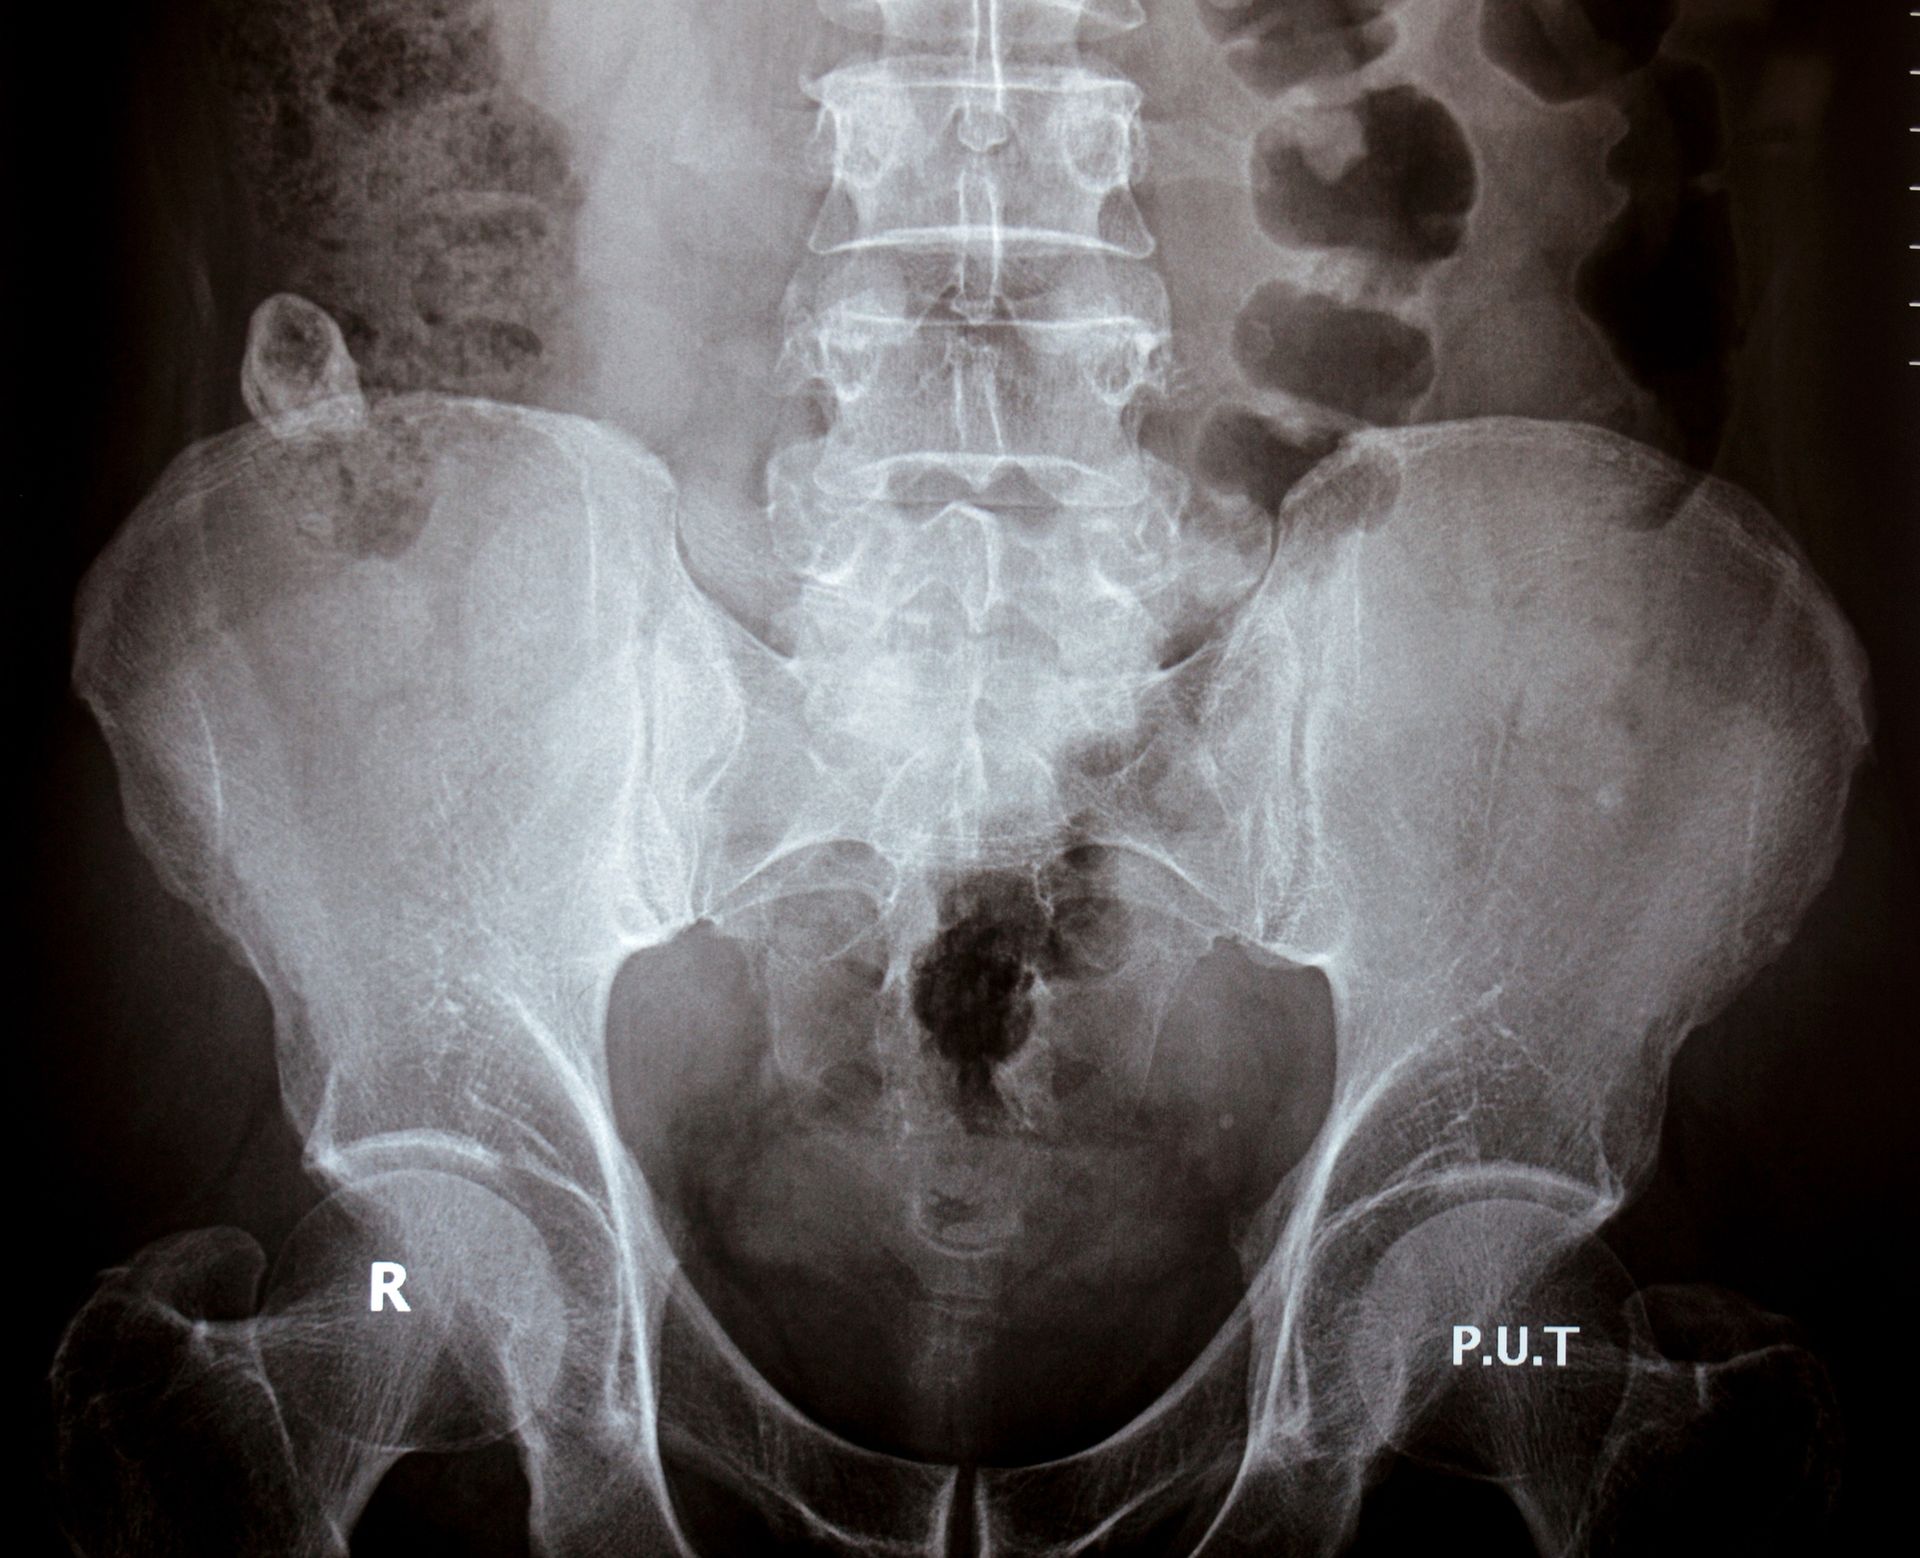

Urografia: caratteristiche, utilizzo e preparazione

L’urografia è un esame radiologico che permette di studiare reni, ureteri e vescica mediante l’iniezione endovenosa di un mezzo di contrasto iodato. Questo consente di visualizzare il percorso del mezzo attraverso le vie escretrici e di ottenere immagini progressive che mostrano eventuali alterazioni anatomiche o funzionali. La tecnica è particolarmente utile per indagare condizioni come calcoli renali, tumori dell’apparato urinario, ipertrofia prostatica, infiammazioni e anomalie della minzione. Uno dei principali vantaggi dell’urografia è la capacità di mostrare in modo diretto il comportamento dell’urina nelle diverse fasi di escrezione, offrendo informazioni diagnostiche dettagliate e preziose per definire il percorso terapeutico.

Per una corretta riuscita dell’esame è necessario che l’intestino sia perfettamente pulito. Nei giorni precedenti l’appuntamento viene suggerita una dieta povera di scorie, mentre il giorno prima può essere previsto l’uso di un lassativo. Il paziente deve inoltre presentarsi a digiuno da almeno otto ore. Durante la procedura, il mezzo di contrasto permette di ottenere immagini sequenziali dei reni e delle vie urinarie, utili per identificare ostacoli al flusso o accumuli sospetti. In alcuni casi, il tecnico può applicare una lieve compressione addominale per migliorare la visualizzazione delle strutture. Pur essendo una tecnica minimamente invasiva, l’urografia fornisce una grande quantità di informazioni diagnostiche, utili per valutare o escludere molte patologie. Al termine dell’esame, il paziente può riprendere normalmente le sue attività quotidiane.